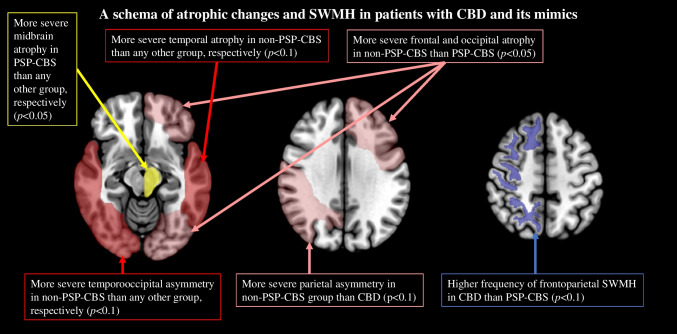

In addition to 19 patients with CBD, 16 with CBD mimics (progressive supranuclear palsy (PSP): 9, Alzheimer’s disease (AD): 4, dementia with Lewy bodies (DLB): 1, frontotemporal lobar degeneration with TAR DNA-binding protein of 43 kDa(FTLD-TDP): 1, and globular glial tauopathy (GGT): 1) were investigated. Compared with the CBD group, the PSP-CBS subgroup showed severe midbrain atrophy without SWMH. The non-PSP-CBS subgroup, comprising patients with AD, DLB, FTLD-TDP, and GGT, showed severe temporal atrophy with widespread asymmetry, especially in the temporal lobes. In addition to over half of the patients with CBD, two with FTLD-TDP and GGT showed SWMH, respectively.

As the main neuropathology of more than half of the patients in the CBD mimics group was PSP, this group was further categorized into PSP-CBS and non-PSP-CBS subgroups. The MRI findings in the CBD and two CBD mimics subgroups are shown in Table 2. Compared with the PSP-CBS subgroup, the CBD group tended to show a higher SWMH ratio (56% vs 0%; p = 0.060). In the CBD group, SWMH was exclusively distributed in the frontal or parietal lobe at high convexity. Its sensitivity, specificity and accuracy to diagnose CBD were 56%, 86%, and 69%, respectively. Compared with the non-PSP-CBS subgroup, the CBD subgroup displayed relatively lower temporal GCA score and degree of asymmetry in the temporal and occipital lobes (0.5 [0.3–1.0] versus 1.5 [1.0–2.3], 0.0 [0.0–0.5] versus 1.0 [0.0–1.5], and 0.0 [0.0–0.0] versus 0.0 [0.0–0.0]; p = 0.073, p = 0.073 and p = 0.082, respectively). Confusable SWMH was detected in one patient with FTLD-TDP and one with GGT. Among the CBD mimics subgroups, the non-PSP-CBS subgroup showed higher frontal, temporal, and occipital lobe GCA scores (1.5 [1.0–2.5] versus 0.5 [0.5–1.0], 1.5 [1.0–2.3] versus 0.0 [0.0–0.5], and 0.5 [0.0–1.0] versus 0.0 [0.0–0.0]; p = 0.043, p = 0.011, and p = 0.019, respectively). By contrast, the degree of midbrain atrophy was most severe in the PSP-CBS subgroup (2.0 [1.0–2.0] versus 0.0 [0.0–0.3], and 2.0 [1.0–2.0] versus 0.0 [0.0–0.0]; p = 0.016 and p = 0.014, respectively). The (weighted) kappa of the above-mentioned visual analyses for the interrater reliability of the two raters was high, ranging from 0.77 to 1.00 in this study. The representative MRI findings of patients with pathologically confirmed CBD and CBD mimics are presented in Figs. 5, 6, 7 and 8.

This study aimed to differentiate patients with pathologically confirmed CBD from those with CBD mimics using semiquantitative visual rating scales. Various rating scales reflecting the degree of atrophy and asymmetry were not useful for differentiating CBD and its mimics. Conversely, the abnormal subcortical white matter signal on axial FLAR (i.e., SWMH) was higher in patients with CBD than those with its mimics. Furthermore, severe midbrain in patients with the PSP-CBS subgroup, and severe temporal atrophy and widespread asymmetry in patients with the non-PSP-CBS subgroup were higher than those in patients with CBD. These results suggest that SWMH and particular atrophic distribution could be a valuable contributor to the differentiation between CBD and its mimics (Fig. 9).